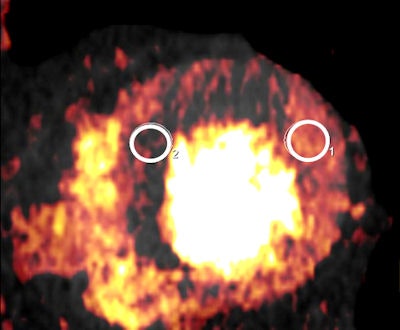

The researchers equipped an anthropomorphic phantom with tubular inserts containing known iodine concentrations from 20 mL in the cardiac chamber, and fat rings to simulate different patient sizes. Dedicated software was used to measure iodine concentrations at DECT and the results were compared to true concentrations. Linear regression models to identify predictors of measurement accuracy.

The results showed excellent correlation between measured and true iodine concentrations in 72 datasets across both CT systems and multiple protocols ( r = 0.994 - 0.997, p < 0.0001). The mean measurement errors between real and measured CT values were 3.0 ± 7.0 % for first-generation scanners and -2.9 ± 3.8 % for second-generation dual-source CT.

The group also reported a significant (p = 0.002) interaction between true iodine concentration and phantom size, and measurement accuracy decreased with increasing phantom size. The mean error was -0.8 ± 3.9% without the fat ring simulating larger patients, 2.0 ± 4.9 % when a five-cm fat ring was used, and 8.3% when a 10-cm fat ring was used. And overall accuracy of iodine measurements was better for 100 kVp than for 80 kVp, especially at lower iodine concentrations, the study team wrote.